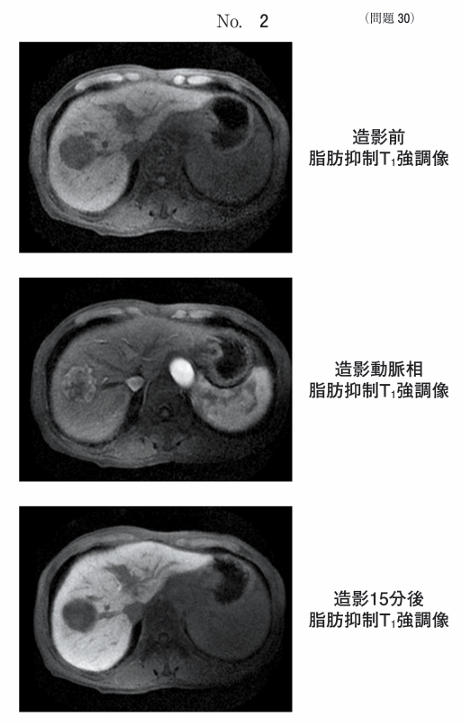

午前/問題30

肝細胞癌患者の同一断面のMR像別冊No. 2を別に示す。使用した造影剤はどれか。

1.塩化マンガン四水和物液

2.フェルカルボトラン注射液

3.クエン酸鉄アンモニウム散剤

4.ガドペンテト酸ジメグルミン(Gd-DTPA)

5.ガドキセト酸ナトリウム(Gd-EOB-DTPA)